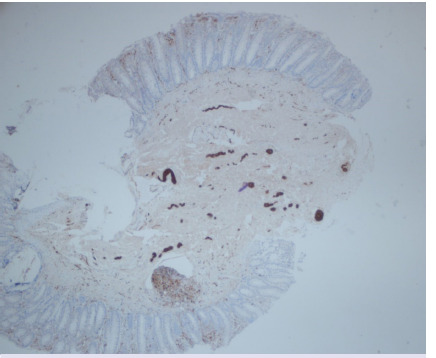

Results: 107 patients were included. There were 66 men (61.6%) and 41 women (38.3%). The median age at biopsy was 15 (1-196) months. FTRB was performed in 81 patients who were unable to pass meconium in the first 48 hours or had intractable constipation. A stoma was performed in 26 patients before the rectal biopsy. Contrast colon radiography was conducted in 61 patients and/or anorectal manometry in 32 patients. Of the biopsies, 74 were full-thickness while 33 were not. Biopsies were repeated in 12 patients. Of the 49 (45%) patients with aganglionic specimens, data about nerve hypertrophy was reported in 37. Among these, 33 had nerve hypertrophy and 4 did not. A definitive surgery was performed in 44 of the 49 patients diagnosed with Hirschsprung disease (HD). Complications were observed in 7 (6.5%) of the patients.

Conclusion: HD was histopathologically diagnosed. Biopsies that are not full-thickness can be of value when using immunohistochemistry stains.